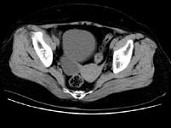

- 单项选择题女,27岁, 体检时B超发现右侧附件区囊性占位性病变,CT检查如图, 下列说法错误的是 ( )

A、病灶来源于右侧卵巢

B、病灶边界清晰

C、病灶为单房,壁薄,无分隔

D、考虑为卵巢浆液性囊腺瘤

E、考虑为卵巢囊肿